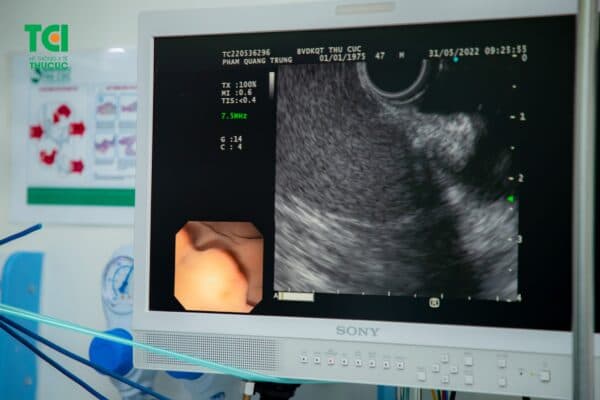

2.4. Siêu âm nội soi xác định mức độ xâm lấn

Để thực hiện siêu âm nội soi, bác sĩ sẽ đổi qua một dây soi khác có gắn thiết bị siêu âm chuyên biệt. Kỹ thuật siêu âm nội soi (EUS) sẽ giúp đánh giá đúng về mức độ xâm lấn của tổn thương tới lớp niêm mạc, từ đó chẩn đoán về giai đoạn ung thư sớm.

Siêu âm nội soi giúp xác định về mức độ xâm lấn của tổn thương.